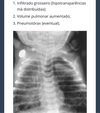

Clinica pneumonia grave